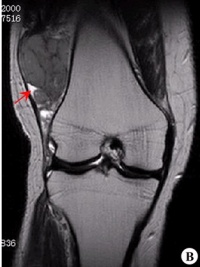

滑膜肉瘤起源于滑膜、滑囊和腱鞘,是发生频率较高的一种软组织肉瘤以四肢最好发,尤其是膝关节,外与关节无关的部位如头颈部、腹壁、后腹膜也可发生。 全身凡有关节滑膜、滑囊、腱鞘均可受累,一般原发于关节囊外,后穿入关节囊。可发于任何年龄,但以20~40岁见。男多于女,病理长短不等,以1年左右多见。

滑膜肉瘤是发生频率较高的一种软组织肉瘤,好发于15-40岁,四肢的大关节附近,特别是膝关节附近好发,另外与关节无关的部位如头颈部、腹壁、后腹膜也可发生。本病的基本X线表现有三点:软组织肿块,局部骨皮质破坏,肿瘤的钙化和骨化。此病好发于关节附近,呈分叶结节状,密度增高,边界清楚的软组织肿块。其内可见骨化影,呈条状或块状轮廓清楚的高密度影,部分骨化影中可见骨小梁结构,少数病例为骨化性肿块。应与骨旁骨肉瘤、骨化性肌炎、骨肉瘤等鉴别。

临床表现为关节附近的无痛肿块,患者可能出现关节周围肿胀或肿块,肿块可沿软组织伸展至整个前臂。在肿块皮肤表面可能有静脉怒张。肿块质地大多为中等,也有较硬和较软。会出现不同程度疼痛、隐痛或钝痛,甚至后期呈剧烈疼痛,夜间疼痛显著。有些患者局部肢体活动受限。在四肢关节附近,以局部肿胀、肿块、疼痛,活动受限为主要临床症状,以软组织肿块、肿块钙化、骨骼改变及骨膜反应为主要X线表现。恶性滑膜瘤临床X线表现不典型而易误诊、漏诊。

(1)软组织肿块。临床所能触及的肿块并不都在X线上显示出来。有的表现局部软组织肿胀,有的出现软组织肿块。一般肿块密度较邻近软组织稍高,大小不等,小的只有豌豆大,大者可巨大,有跨越关节生长的特点。

(2)软组织肿块钙化。软组织肿块内可见到不定形、不规则钙化影,占30%。钙化的原因可能与出血、感染、坏死及软骨钙化等有关,且钙化的多少与肿瘤恶性度有关,钙化越少,恶性度越高。

(3)骨骼改变。会出现不同程度骨质压迫、缺损或溶骨性破坏。譬如骨质疏松,骨萎缩畸形,囊性骨缺损,骨质糜烂,溶骨性破坏,关节改变。骨质轻度疏松为早期表现,以后压迫性骨萎缩、变细或囊性缺损,进一步发展出现骨质破坏。骨破坏大多呈不规则状,也可呈囊状,跨关节者可侵及多骨。本病一般关节无改变,但偶尔可有侵入关节,使间隙增宽或出现软组织肿块,也可出现关节积液,易误诊为关节疾患。

(4)骨膜反应。可出现平行、花边状或针状骨膜反应,有些虽未见到明确骨膜反应,但邻近骨皮质可见到刺状突起。可能出现Codman三角。